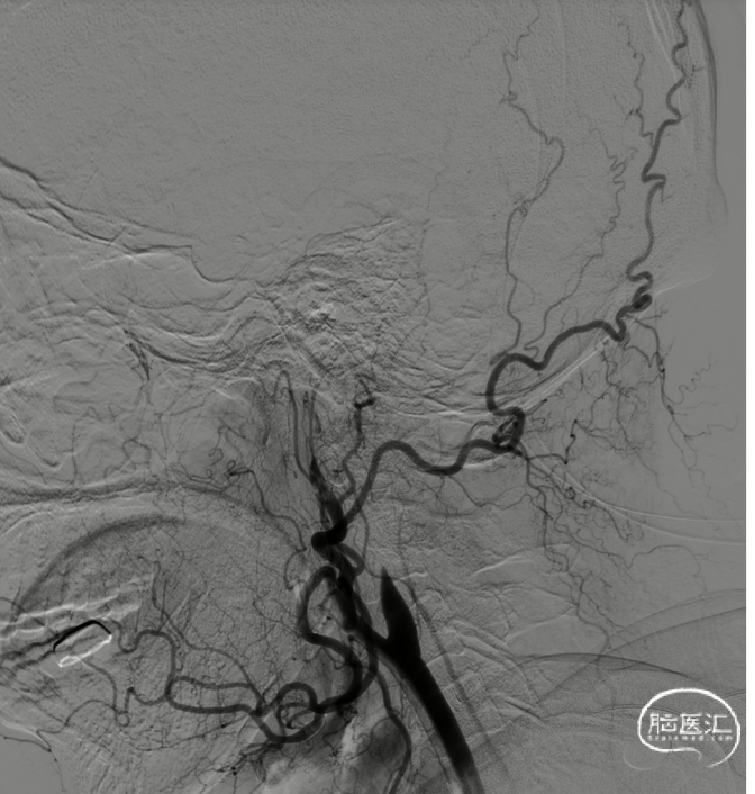

术前造影

右侧颈内动脉闭塞,同时颈外动脉有血栓,闭塞。

右侧颈内动脉起始部呈现“火焰征”,提示假性闭塞,远端眼动脉未见代偿。

前交通开放,左侧A1供应双侧A2。

后交通动脉开放,右侧大脑中动脉可见部分显影。

提示病变为栓塞性串联病变,增加手术难度。这样我们就考虑首先争取单纯抽吸快速开通颈内动脉,然后再SWIM技术取通大脑中动脉。